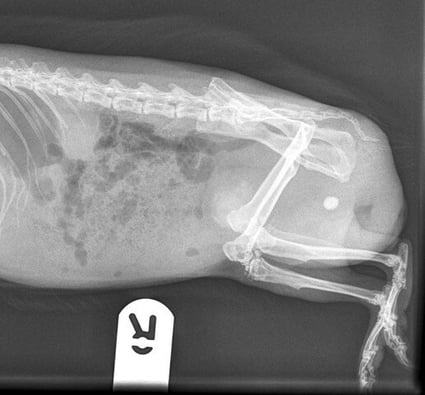

Radiographs of the caudal abdomen are a useful diagnostic tool, as the calcium carbonate “sludge” sits as a radiopaque shadow in the gravity-dependent area of the bladder lumen

Radiographs of the caudal abdomen are a useful diagnostic tool, as the calcium carbonate “sludge” sits as a radiopaque shadow in the gravity-dependent area of the bladder lumen (Figure 2). Ultrasonography should be used to confirm the presence of bladder “sludge”, which often appears as heterogenous swirling material within the bladder lumen, as well as to identify if any uroliths are present within the “sludge” itself. Urinalysis will show crystalluria, often accompanied by proteinuria and haematuria (Di Girolamo and Selleri, 2020). This can also help to identify the presence of bacteria; however, this should be interpreted with caution in free-catch samples.